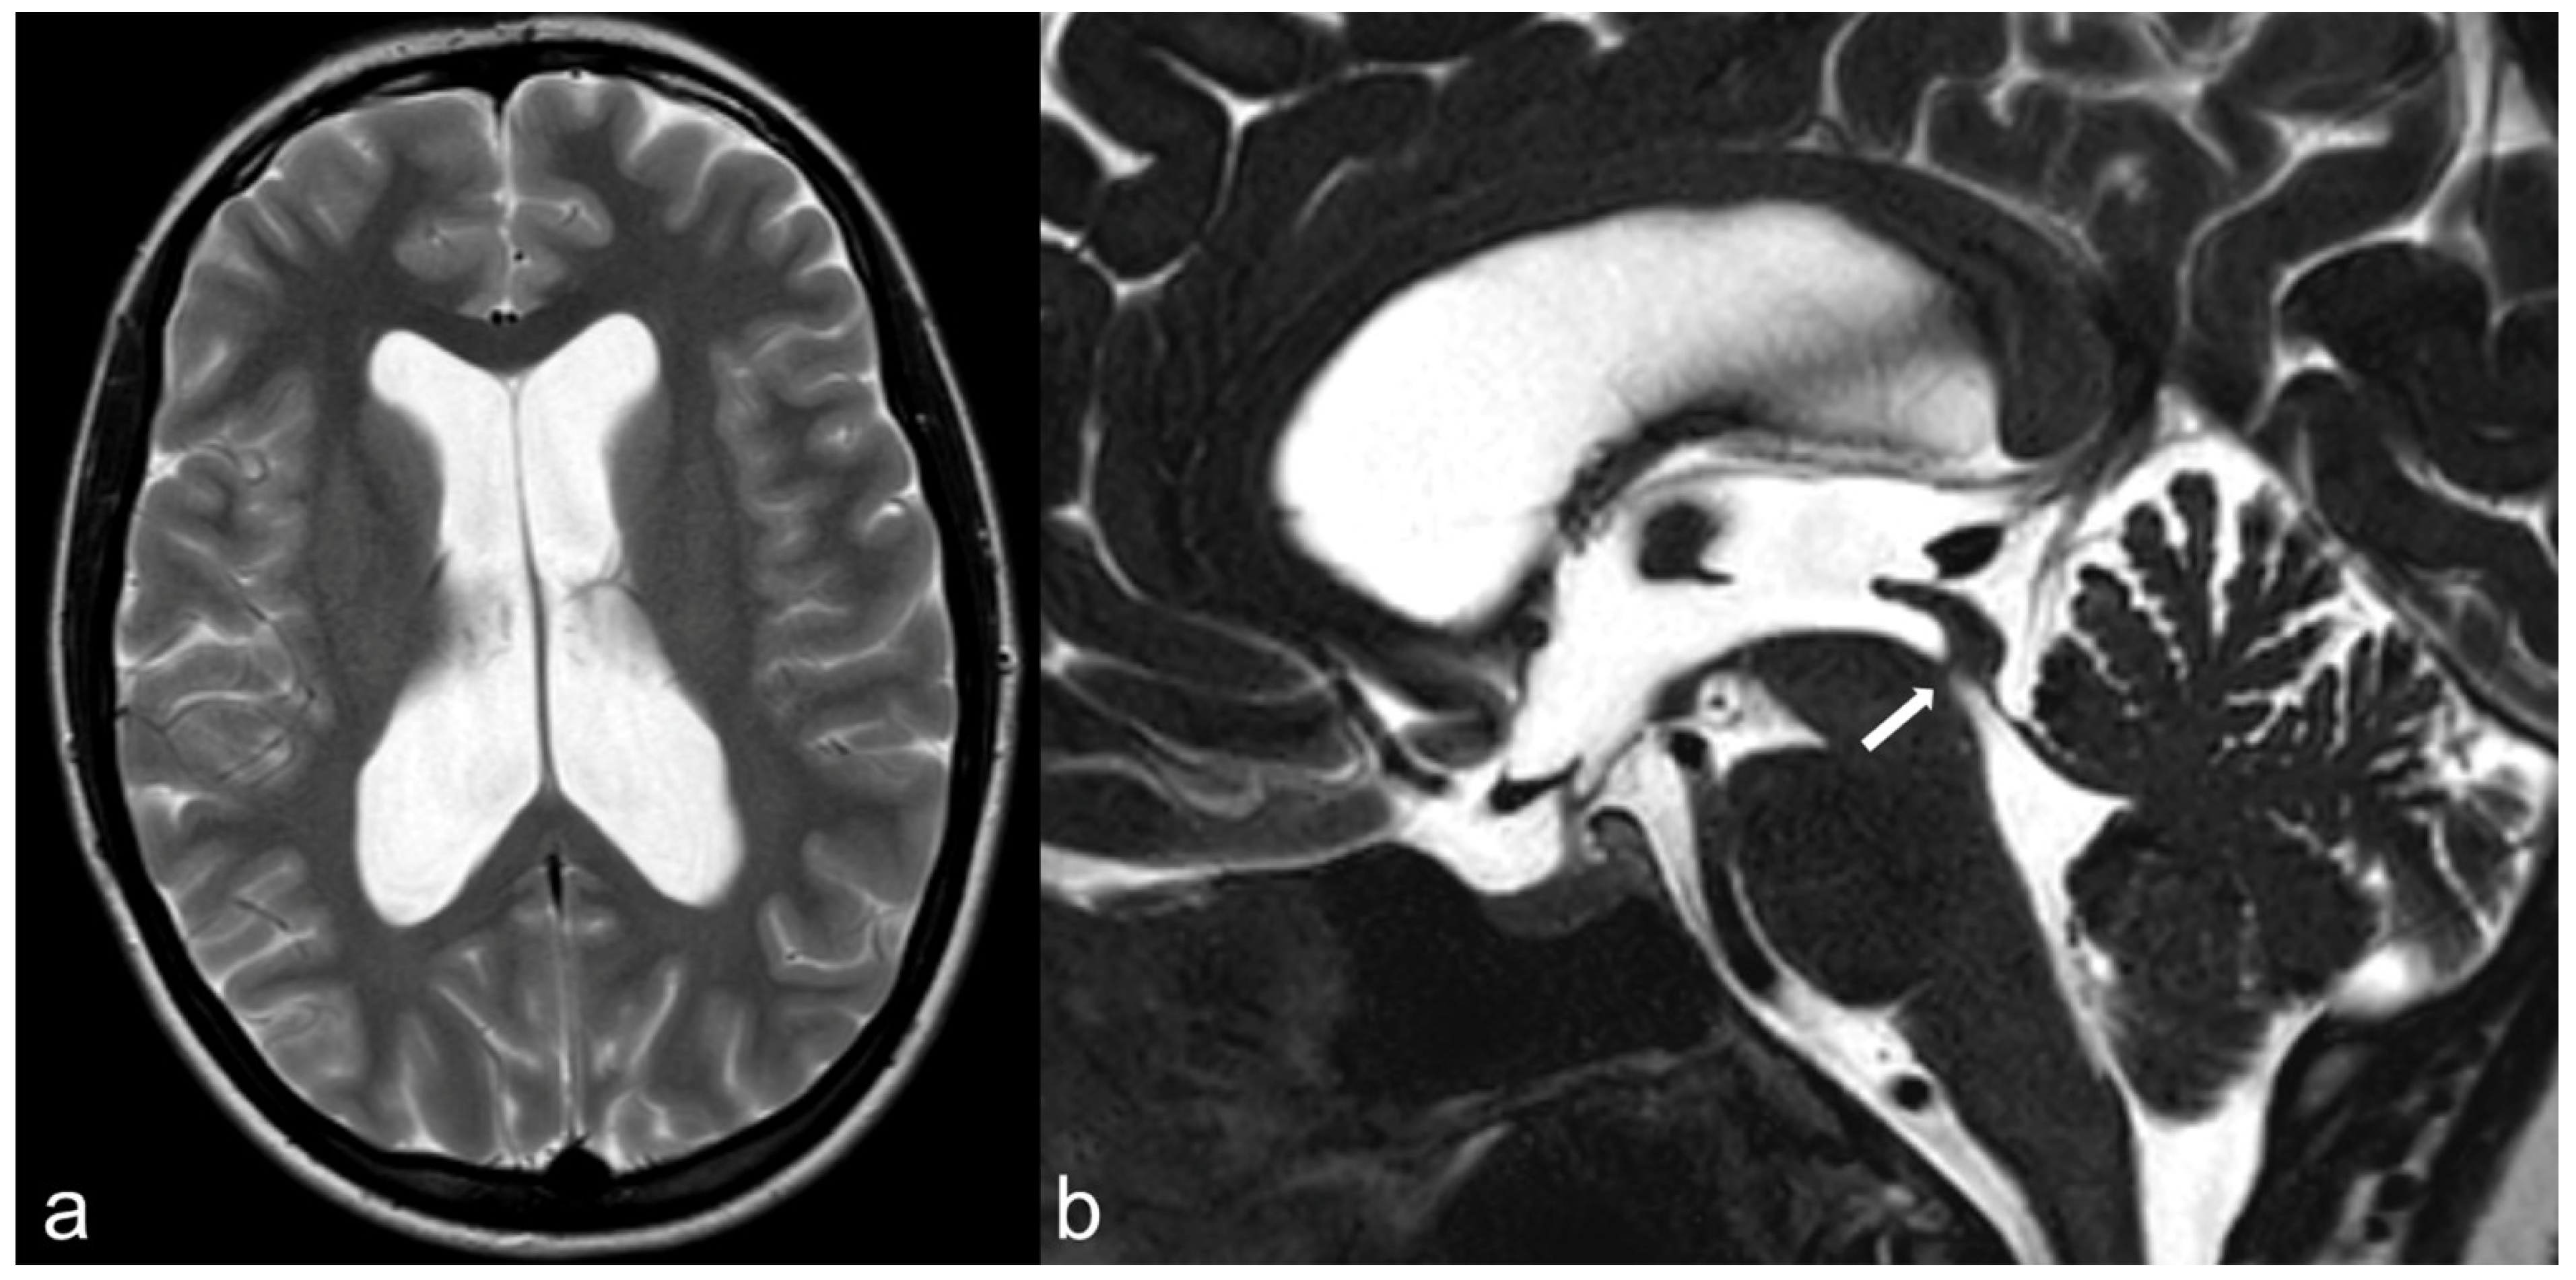

3.5. Hydrocephalus, Ventricular System and Subarachnoid Cisterns

3.10. Cranio-Cervical Malformations (Chiari I)

3.12. Neonatal and Fetal MRI